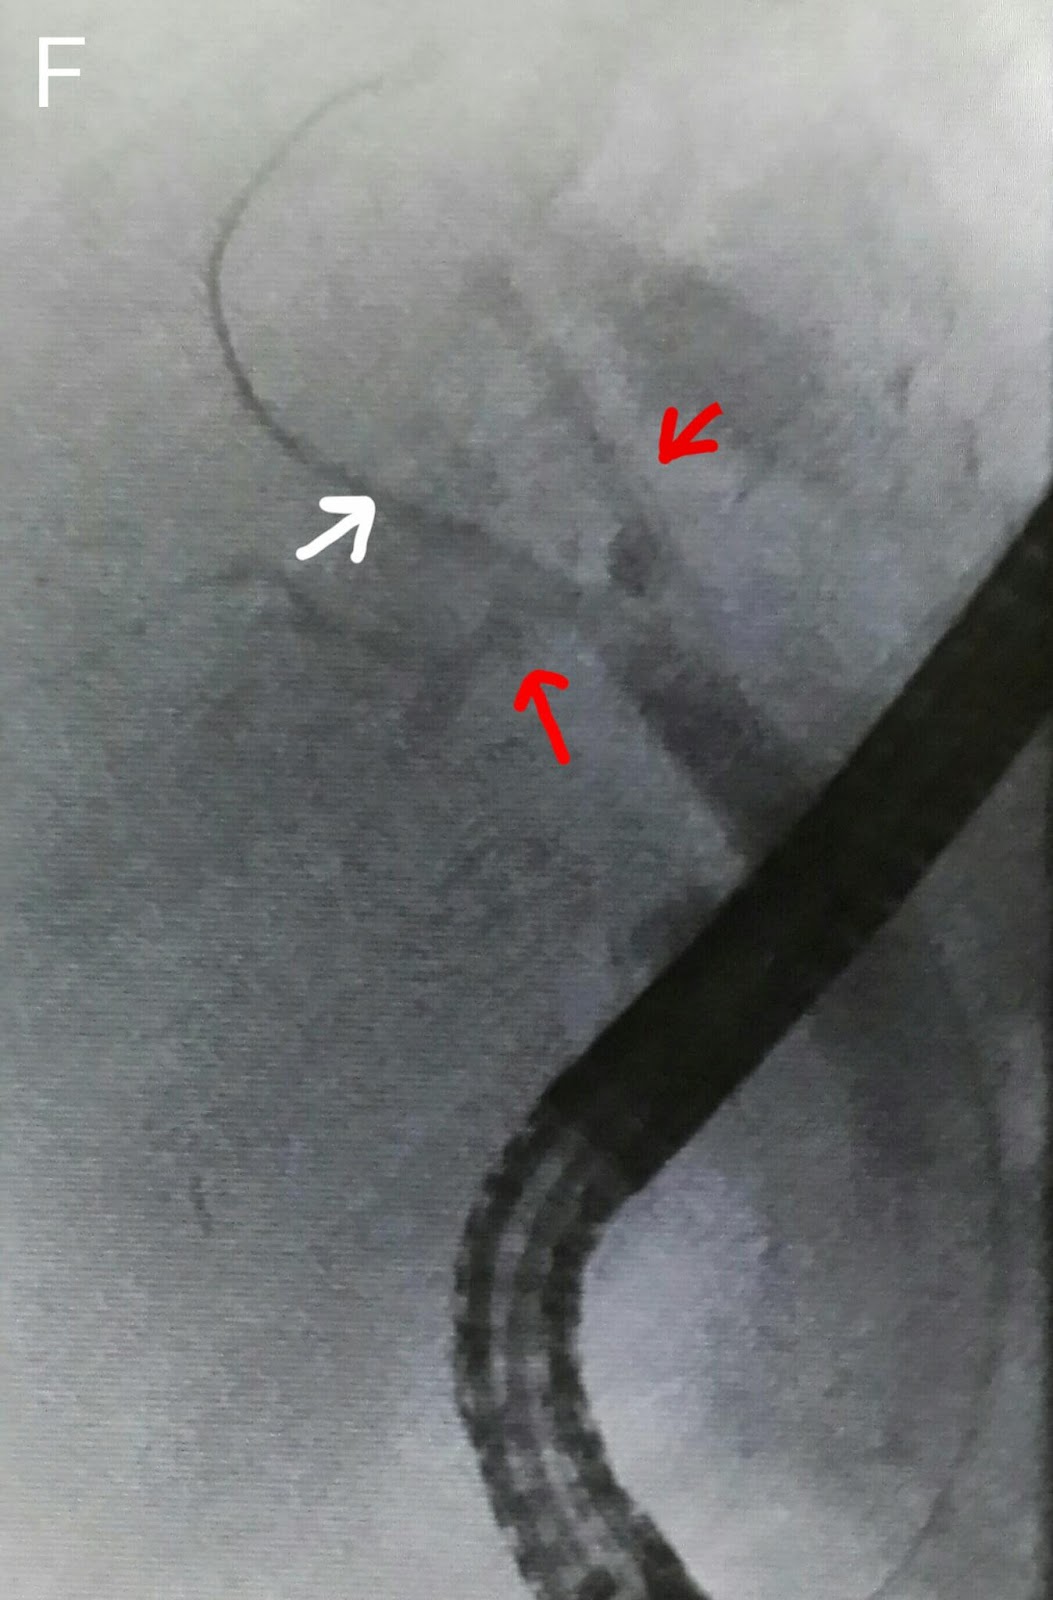

This 45 year old gentleman had suffered from bile duct injury whilst undergoing an open cholecystectomy 10 months ago. The surgeons placed a drain (A: red arrow shows the drain. White arrow shows the large leak-almost looking like the gallbladder in shape. Blue arrow shows the main bile duct). An MRI was done soon after and confirmed the leakage (B: red arrows show the bile leak). He was reffered to our facility and we had placed a 10 French 10cm long plastic stents to bridge the leak. (C: white arrows show the stent) . This was about ten months ago. He was then lost to follow up. He resurfaced at our outpatient out of curiosity asking what was to be done about the Stent we had placed. When questioned as to why he hadn't turned up a month after the procedure, he said he had been told by his physician that his condition has been cured and he needs no more treatment. The moment we went in for ERCP, we were greeted by a normal ampulla with no sign of his placed stent. We thought it had migrated inwards but that wasn't the case as it didn't show up on flouroscopy either. One thing we noted was almost absent bike flow from the ampulla and normal flow from another opening just above it (D: Blue arrow marks the ampulla and white arrow indicates the second opening above it with smeared bile). This second opening was obviously a fistula. Cannulation and contrast injection showed no bile leakage (E: white arrows show the bile duct. Even the fistulous track wasn't outlined). We concluded that the Stent had slipped out and his bole was driving through the fistula. The procedure was ended by a sphincterotomy which was extended to include the fistulous opening above the ampulla (F: white arrow).

We then accessed the CBD (F: blue arrow shows the papillotome in the CBD. White arrow marks the opening of the pancreatic duct in the papilla). Contrast injection outlined a clear bile duct (G: red arrows show the bile duct. White arrows show the contrast in the pancreatic duct). The CBD was swept with balloon.